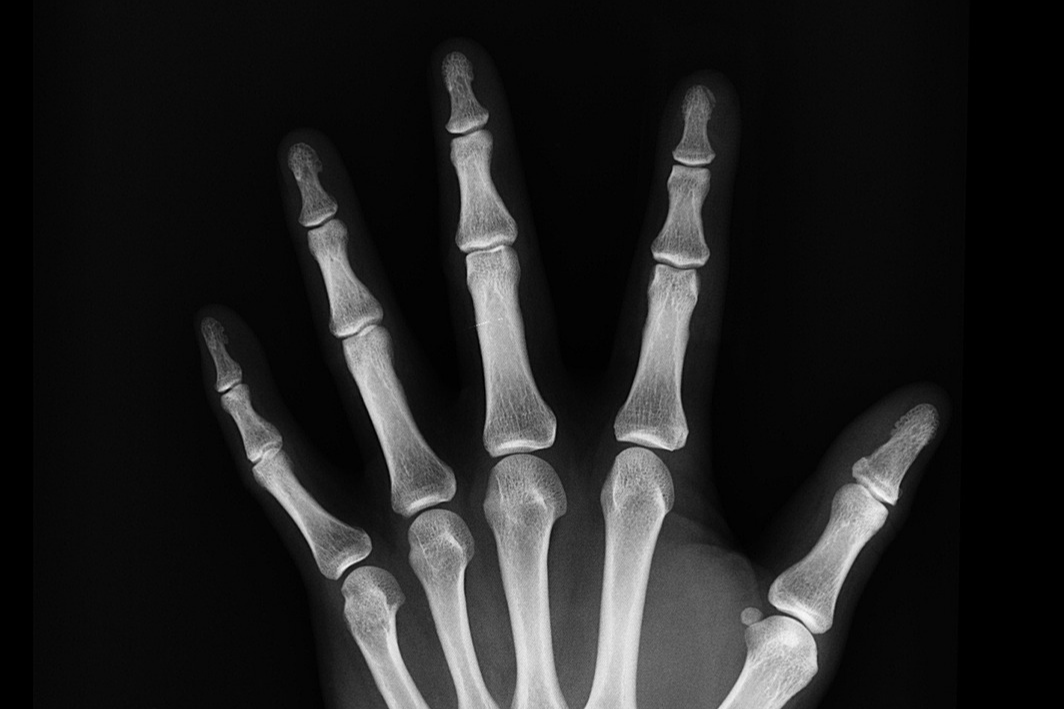

🔹 X-ray 촬영 후 골절 상태 확인

🩺 골절의 종류와 특징

골절의 형태에 따라 치료 방법이 달라지므로 정확한 진단과 치료가 필수적입니다.